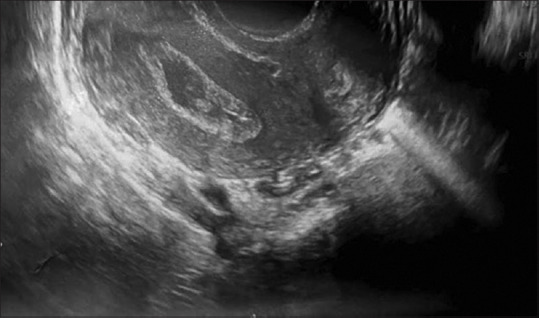

Uterine cervical canal stenosis can lead to significant complications, particularly in the context of active clinical tuberculosis. This case study discusses a 25-year-old woman with undiagnosed clinical tuberculosis who presented with amenorrhea and persistent abdominal pain. Further evaluation revealed uterine cervical canal stenosis and frozen pelvis. Surgical intervention was necessary after confirming the diagnosis through clinical assessment. A laparotomy with hysterotomy was performed, during which a Foley's catheter was used to create a patent uterocervical channel. This innovative approach successfully alleviated her abdominal pain and restored her menstrual function. The patient's recovery was smooth, and her symptoms improved markedly. This case underscores the importance of recognizing cervical stenosis as a potential consequence of tuberculosis and demonstrates the effectiveness of surgical treatment in managing complex cases without resorting to hysterectomy or bilateral salpingo-oophorectomy, thereby preserving reproductive potential for women of childbearing age.